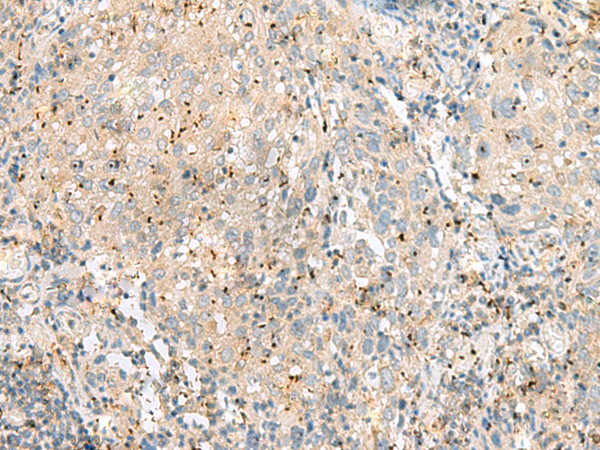

分类: 科研抗体货号: P43576别名: EIF3EIP; EIF3S11; HSPC021; HSPC025; MSTP005; EIF3S6IP应用: IHC反应种属: Human, Mouse

分类: 科研抗体货号: P43586别名: GPCR; PGR7; GALR4; GALRL; GPCR-2037应用: IHC反应种属: Human

分类: 科研抗体货号: P43585别名: ZAQ; PKR1; GPR73; PK-R1; GPR73a应用: IHC反应种属: Human